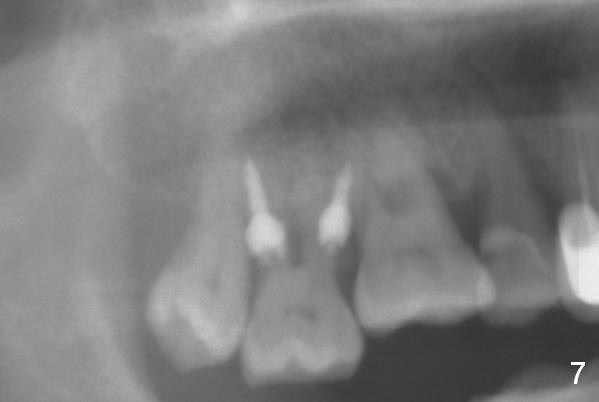

The buccal implant becomes loose in 2-3 months. When the wound heals (Fig.9 <), a 1.6x`10 mm implant is placed with the help of PAs for trajectory (Fig.10,11) and in the nonkeratinized gingiva (higher, the crestal bone may have been traumatized by previous implant placement, Fig.12). Two months later, the tooth #2 is partially intruded (Fig.13). A provisional (Fig.14 P) is fabricated in the osteointegrated implant at #31 with supraocclusion so that the remaining dentition has no occlusal contact (*). The periodontally compromised tooth #2 becomes in buccoversion in 2 months. The provisional is removed, while a lingual button is placed in the buccal surface of the tooth #2 (Fig.15). With power chain attached to the lingual mini-implant, the tooth #2 is lingualized in 2 months. The provisional and the implants are reused for final intrusion (Fig.16). The treatment is nearly 11 months. The buccal implant, although placed in the movable mucosa, remains stable and healthy (Fig.17). The tooth #1, as a guiding plane (to prevent #2 from distalization during intrusion), is not extracted after intrusion is completed.